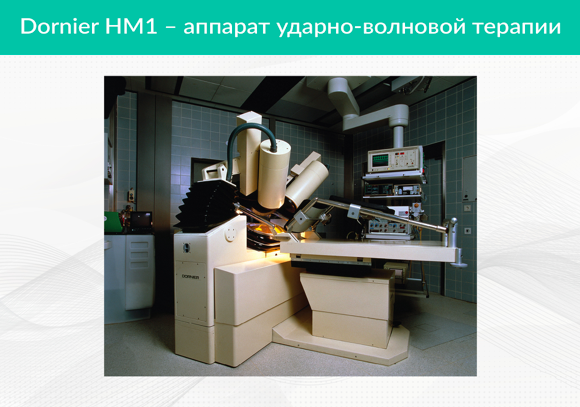

В начале 1950-х годов американский изобретатель Фрэнк Рейбер (Frank Rieber) придумал первый генератор ударных волн. Идея этого аппарата заключалась в создании фокусированных импульсов ударных волн с последующей их передачей в глубины человеческого тела. Первое биологическое тестирование и лечение пациента прошло в Институте хирургических исследований Мюнхенского университета 07.02.1980 года. Использовался аппарат Dornier HM1.

В начале 80-х годов XX века у профессора Ф. Эйзенбергера в урологическом отделении больницы Катарирен в Штутгарте был установлен первый серийный литотриптер нового поколения — Dornier HM3. Сам метод был одобрен FDA только в 1986 году.